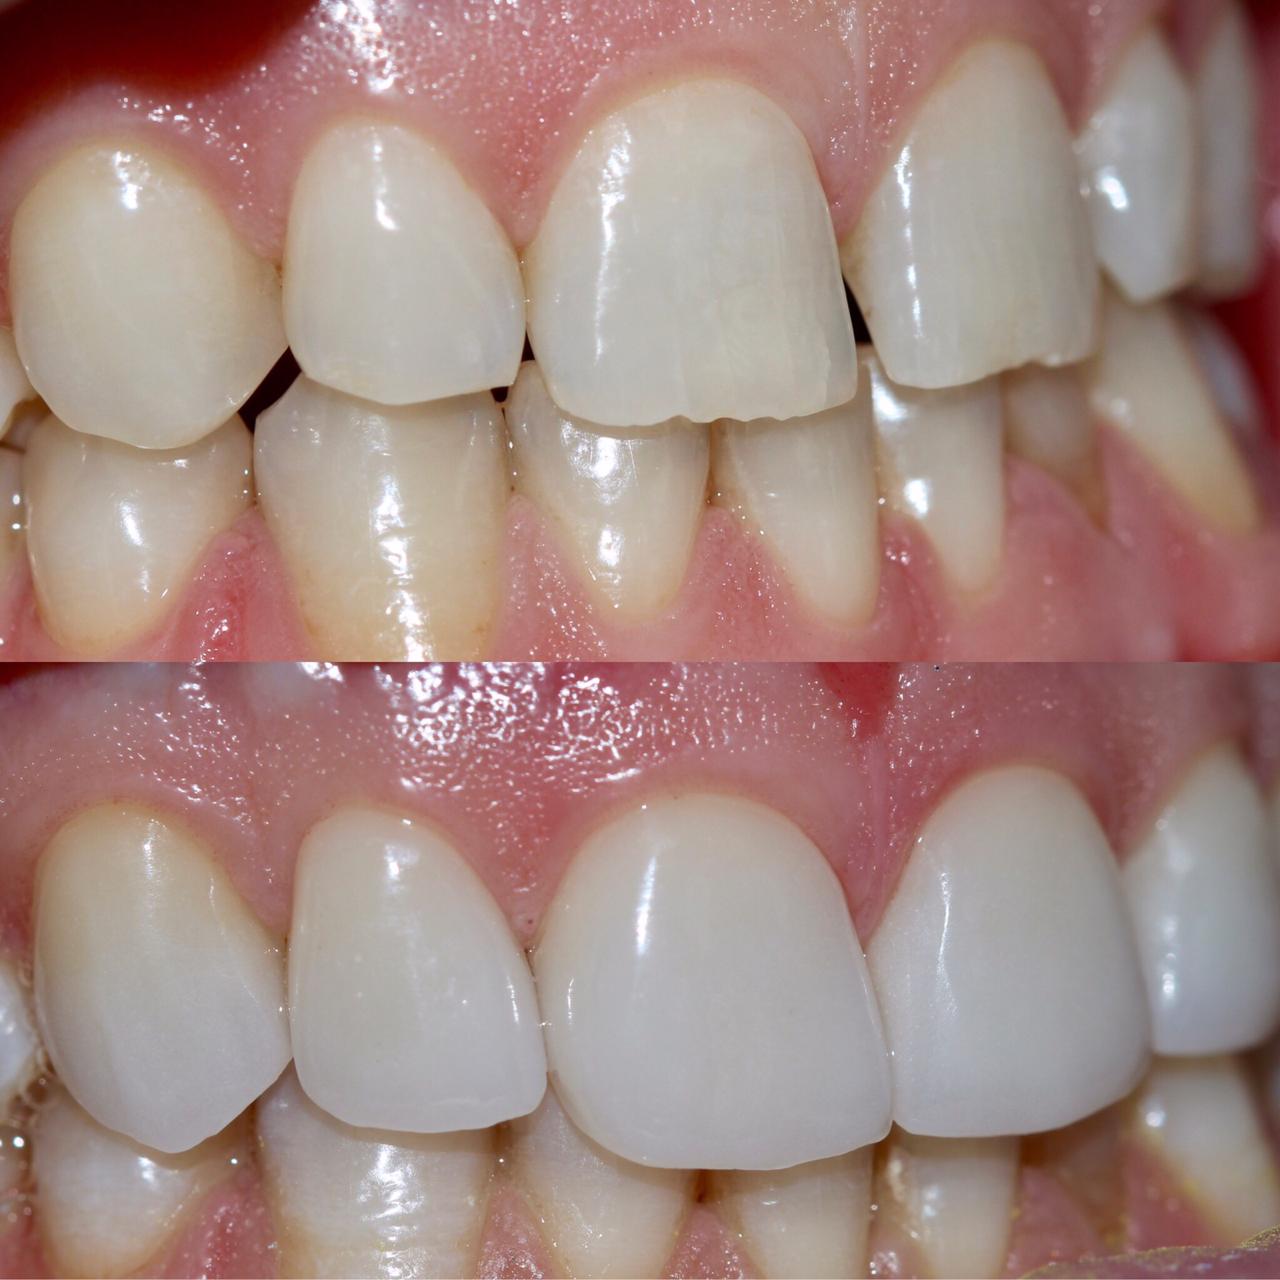

Снова виниры

Замена старых виниров темного цвета на более светлые по причине оголения шейки зуба.

Виниры цвета BLEACH

Установлены керамические виниры на верхнюю челюсть по эстетическим требованиям.